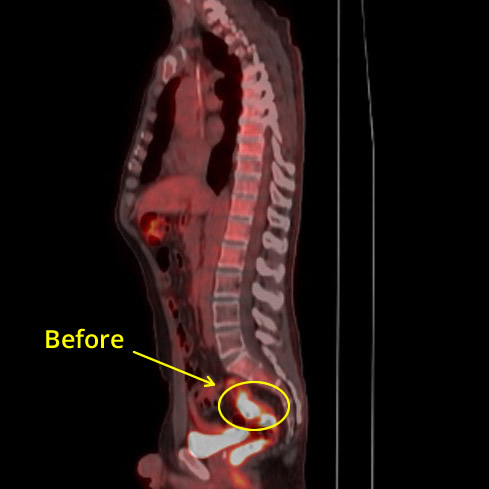

Liver CXR Before